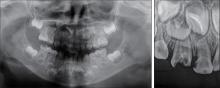

目的 应用口腔全景曲面体层片研究乳尖牙双根的发生率和特征。 方法 收集3~9岁儿童的口腔全景曲面体层片,共纳入100 976张,观察记录乳尖牙双根的发生情况和分布规律。应用SPSS 25.0统计软件分析所得的数据。查阅乳尖牙双根的报道文献,记录患者资料。 结果 乳尖牙双根的发生率为0.37‰(37/100 976),其中男性发生率为0.59‰(32/54 276),女性发生率为0.12‰(5/46 700),男女间差异有统计学意义(χ2 =15.955,P=0.000)。37例儿童的乳尖牙双根发生数目以1~2颗为主,其中1颗者11例(29.73%),2颗者18例(48.65%)。76颗乳尖牙双根的牙位分布左侧和右侧间差异无统计学意义(χ2 =1.316,P=0.251),上颌和下颌间差异有统计学意义(χ2 =15.213,P=0.000),单侧和双侧间差异有统计学意义(χ2 =6.083,P=0.014)。 结论 乳尖牙双根罕见,发生数目多为1~2颗,男性多于女性,上颌多于下颌,双侧发生多于单侧发生。

Objective The incidence and clinical characteristics of bi-rooted primary canines were investigated by performing oral panoramic radiographs. Methods A total of 100 976 oral panoramic radiograph of subjects aged 3-9 years old were collected, and the incidence and distribution of bi-rooted primary canines were observed and recorded. The obtained data were analyzed using SPSS 25.0 statistical software, and the literature on bi-rooted primary canine was reviewed to record patient’s data. Results The incidence of bi-rooted primary canines was 0.37‰ (37/100 976), of which 0.59‰ (32/54 276) occurred in males and 0.12‰ (5/46 700) in females. Statistically significant difference was observed between males and females (χ2 =15.955, P=0.000). The number of bi-rooted primary canine in 37 children was mainly 1-2. Among them, 11 subjects (29.73%) had one bi-rooted primary canine, and 18 subjects (48.65%) had two bi-rooted primary canines. The tooth position distribution of 76 bi-rooted primary canines showed no significant difference between the left and right sides (χ2 =1.316, P=0.251). However, significant difference was found between the upper and lower jaws (χ2 =15.213, P=0.000) and between the unilateral and bilateral sides (χ2 =6.083, P=0.014). Conclusion Bi-rooted primary canines are rare, mostly occur in 1-2 teeth, and are more common in males than females, in the upper jaw than in the lower jaw, and on both sides than on one side.